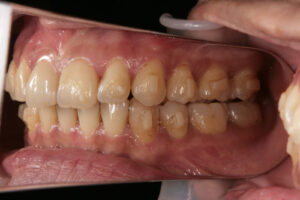

他院のインビザラインで失敗した38歳女性 大阪・梅田・北新地

Invisalign failure

矯正したにも関わらず前歯が噛んでいない

インビザラインで失敗した38歳女性

Invisalign failure - Gum recession1

Invisalign failure – Gum recession1

歯肉が退縮している

Invisalign failure - Gum recession

Invisalign failure – Gum recession

全体的な汚れが目立つ

アタッチメントの下は磨けない

インビザライン矯正失敗」というのは、歯列矯正治療の結果が期待どおりにいかなかった場合を指す言葉です。

失敗と感じるケースにはいくつかのパターンがあり、それぞれ原因や対処法が異なります。

インビザライン治療において歯肉退縮が生じることは稀ですが、可能性はゼロではありません。

歯肉退縮は、歯茎が後退し、歯の根元が露出する状態です。これが起こる原因にはいくつか考えられます。

1. 過度な歯の動き: インビザラインによる歯の移動が過剰だった場合、歯茎に負担がかかり退縮することがあります。

2. 歯周病の既往: 既に歯周病のリスクがある場合、治療中に歯肉退縮が進行しやすくなります。

3. 不適切な口腔ケア: 治療中の口腔衛生管理不足も歯肉退縮の原因となることがあります。

4. 個人の解剖学的要因: 歯茎の厚さや骨の構造によっても影響を受けることがあります。

もし歯肉退縮が疑われる場合は、早めに歯科医師または矯正専門医に相談することをお勧めします。

適切な診断と治療計画の見直しが必要です。

場合によっては、歯周治療や歯肉の再生治療が検討されることもあります。